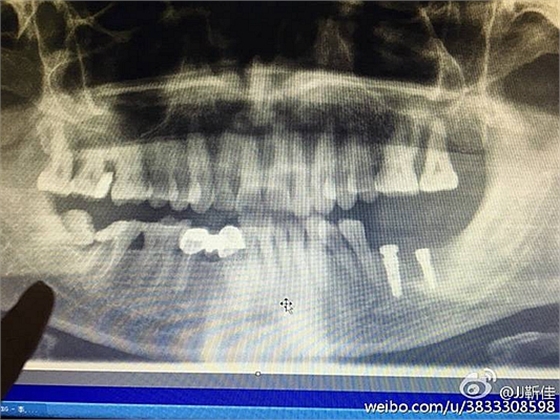

今年的額外牙真多啊 男孩14周。

ct定位

額外牙拔除

好大的額外牙